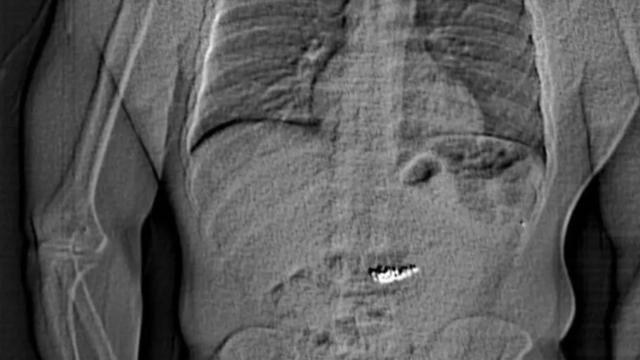

7NEWS.az xəbər verir ki, Florida ştatının Orlando şəhərində bir oğru polis nəzarətinə götürülməzdən əvvəl dəyəri yarım milyon dollardan çox olan oğurlanmış sırğaları udub.